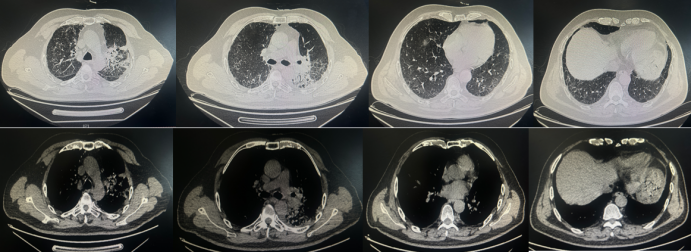

辅助检查:血常规示WBC 2.24×109/LNEU 1.49×109/LLYM 0.46×109/L,仍处于低值Hb 112 g/L;SAA 111.51 mg/LCRP 28.3 mg/LIL-6 10.49 pg/mlPCT 0.1 ng/ml痰培养检出大肠埃希菌。9月2日胸部CT示左肺门肿物较前缩小,伴双肺多发弥漫微小结节(图5)9月10日新冠病毒检测阳性。

图片

5  患者第二次住院胸部CT(2025-09-02)